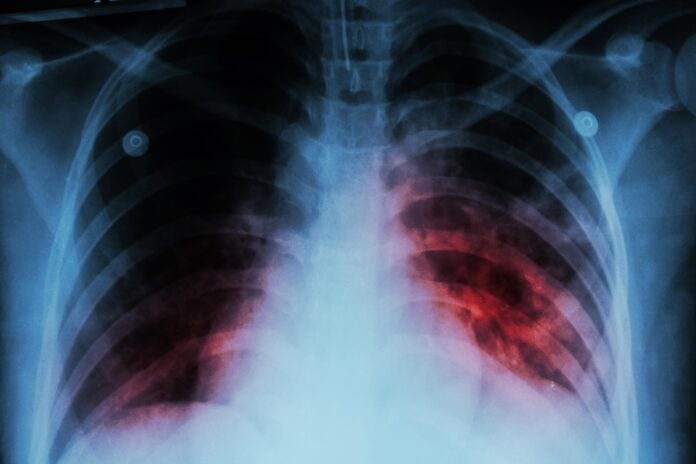

Tuberculosis is a chronic bacterial infection that most commonly affects the lungs but can also involve other parts of the body. It spreads through respiratory droplets released into the air when an infected person coughs or sneezes, although prolonged close contact is generally required for transmission.